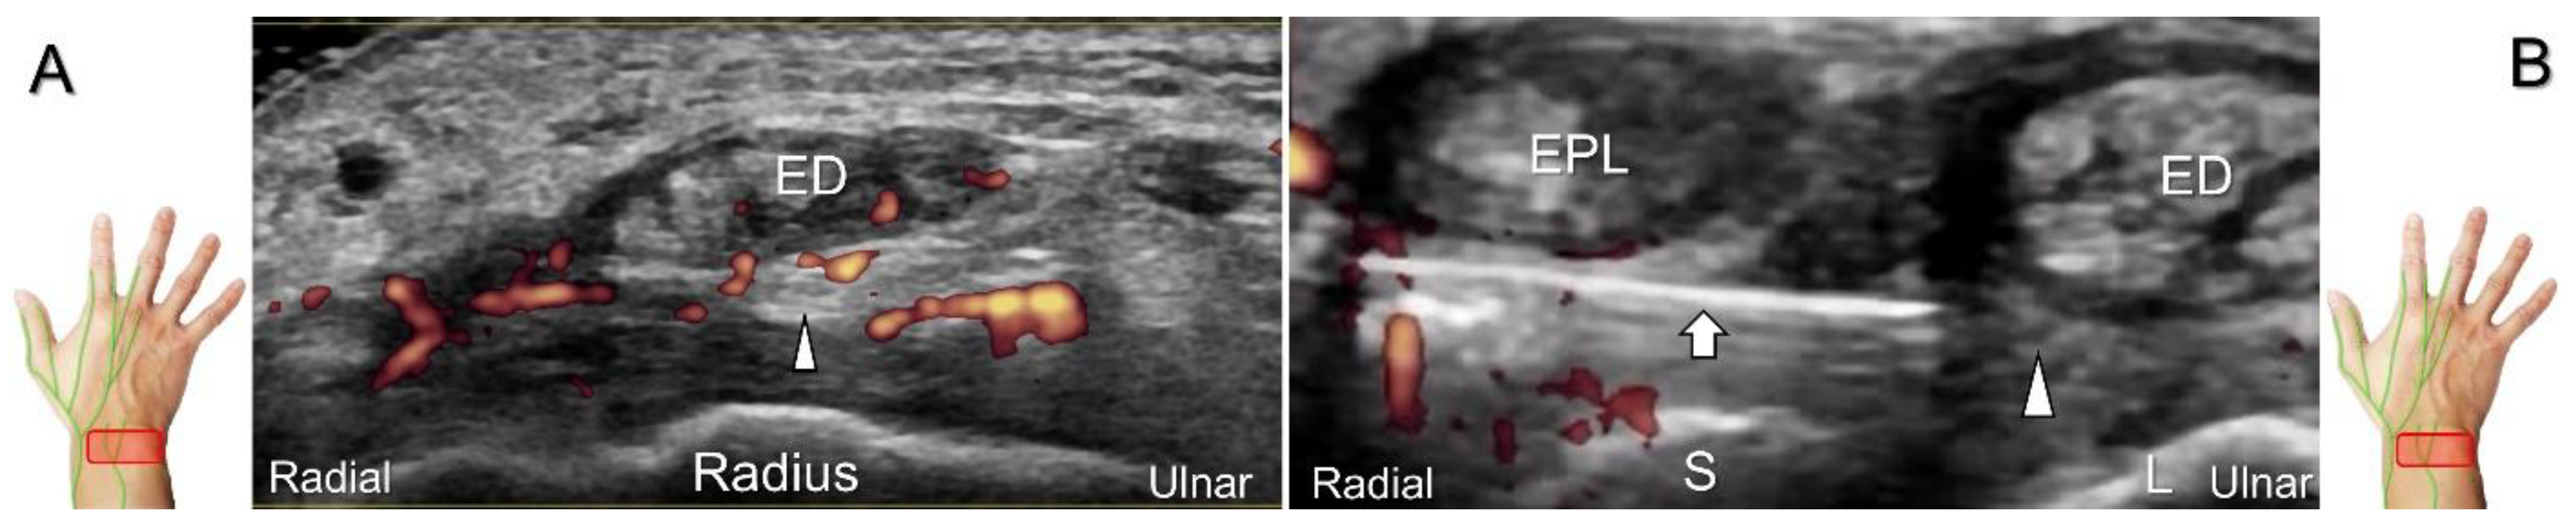

Nerve entrapment can occur from repetitive and forceful use of extensor digitorum longus and extensor pollicis longus muscles. Contusion to the wrist can traumatize the posterior interosseus nerve, leading to neuroma formation (Figure 26B,C). The nerve can also be irritated by hypertrophic synovium secondary to extensor digitorum communis tenosynovitis (Figure 27A) [47]. When injecting the scapho-lunate joint, the nerve should be identified first to avoid iatrogenic injury. In cases suffering from pain or allodynia over the dorsal radioulnar joint, hydrodissection of the nerve can be performed. The in-plane approach during the nerve’s short-axis view is the preferred method (Figure 27B) whereby iatrogenic injury of the vessels and extensor tendons can be prevented.

Figure 27. Sonographic imaging (short-axis view) is performed to assess the posterior interosseus nerve entrapment due to synovitis in rheumatoid arthritis (A). Ultrasound-guided injection (B). Arrowheads: posterior interosseus nerve; arrow: needle; EPL: extensor pollicis longus tendon; ED: extensor digitorum communis tendon; S: scaphoid; L: lunate.